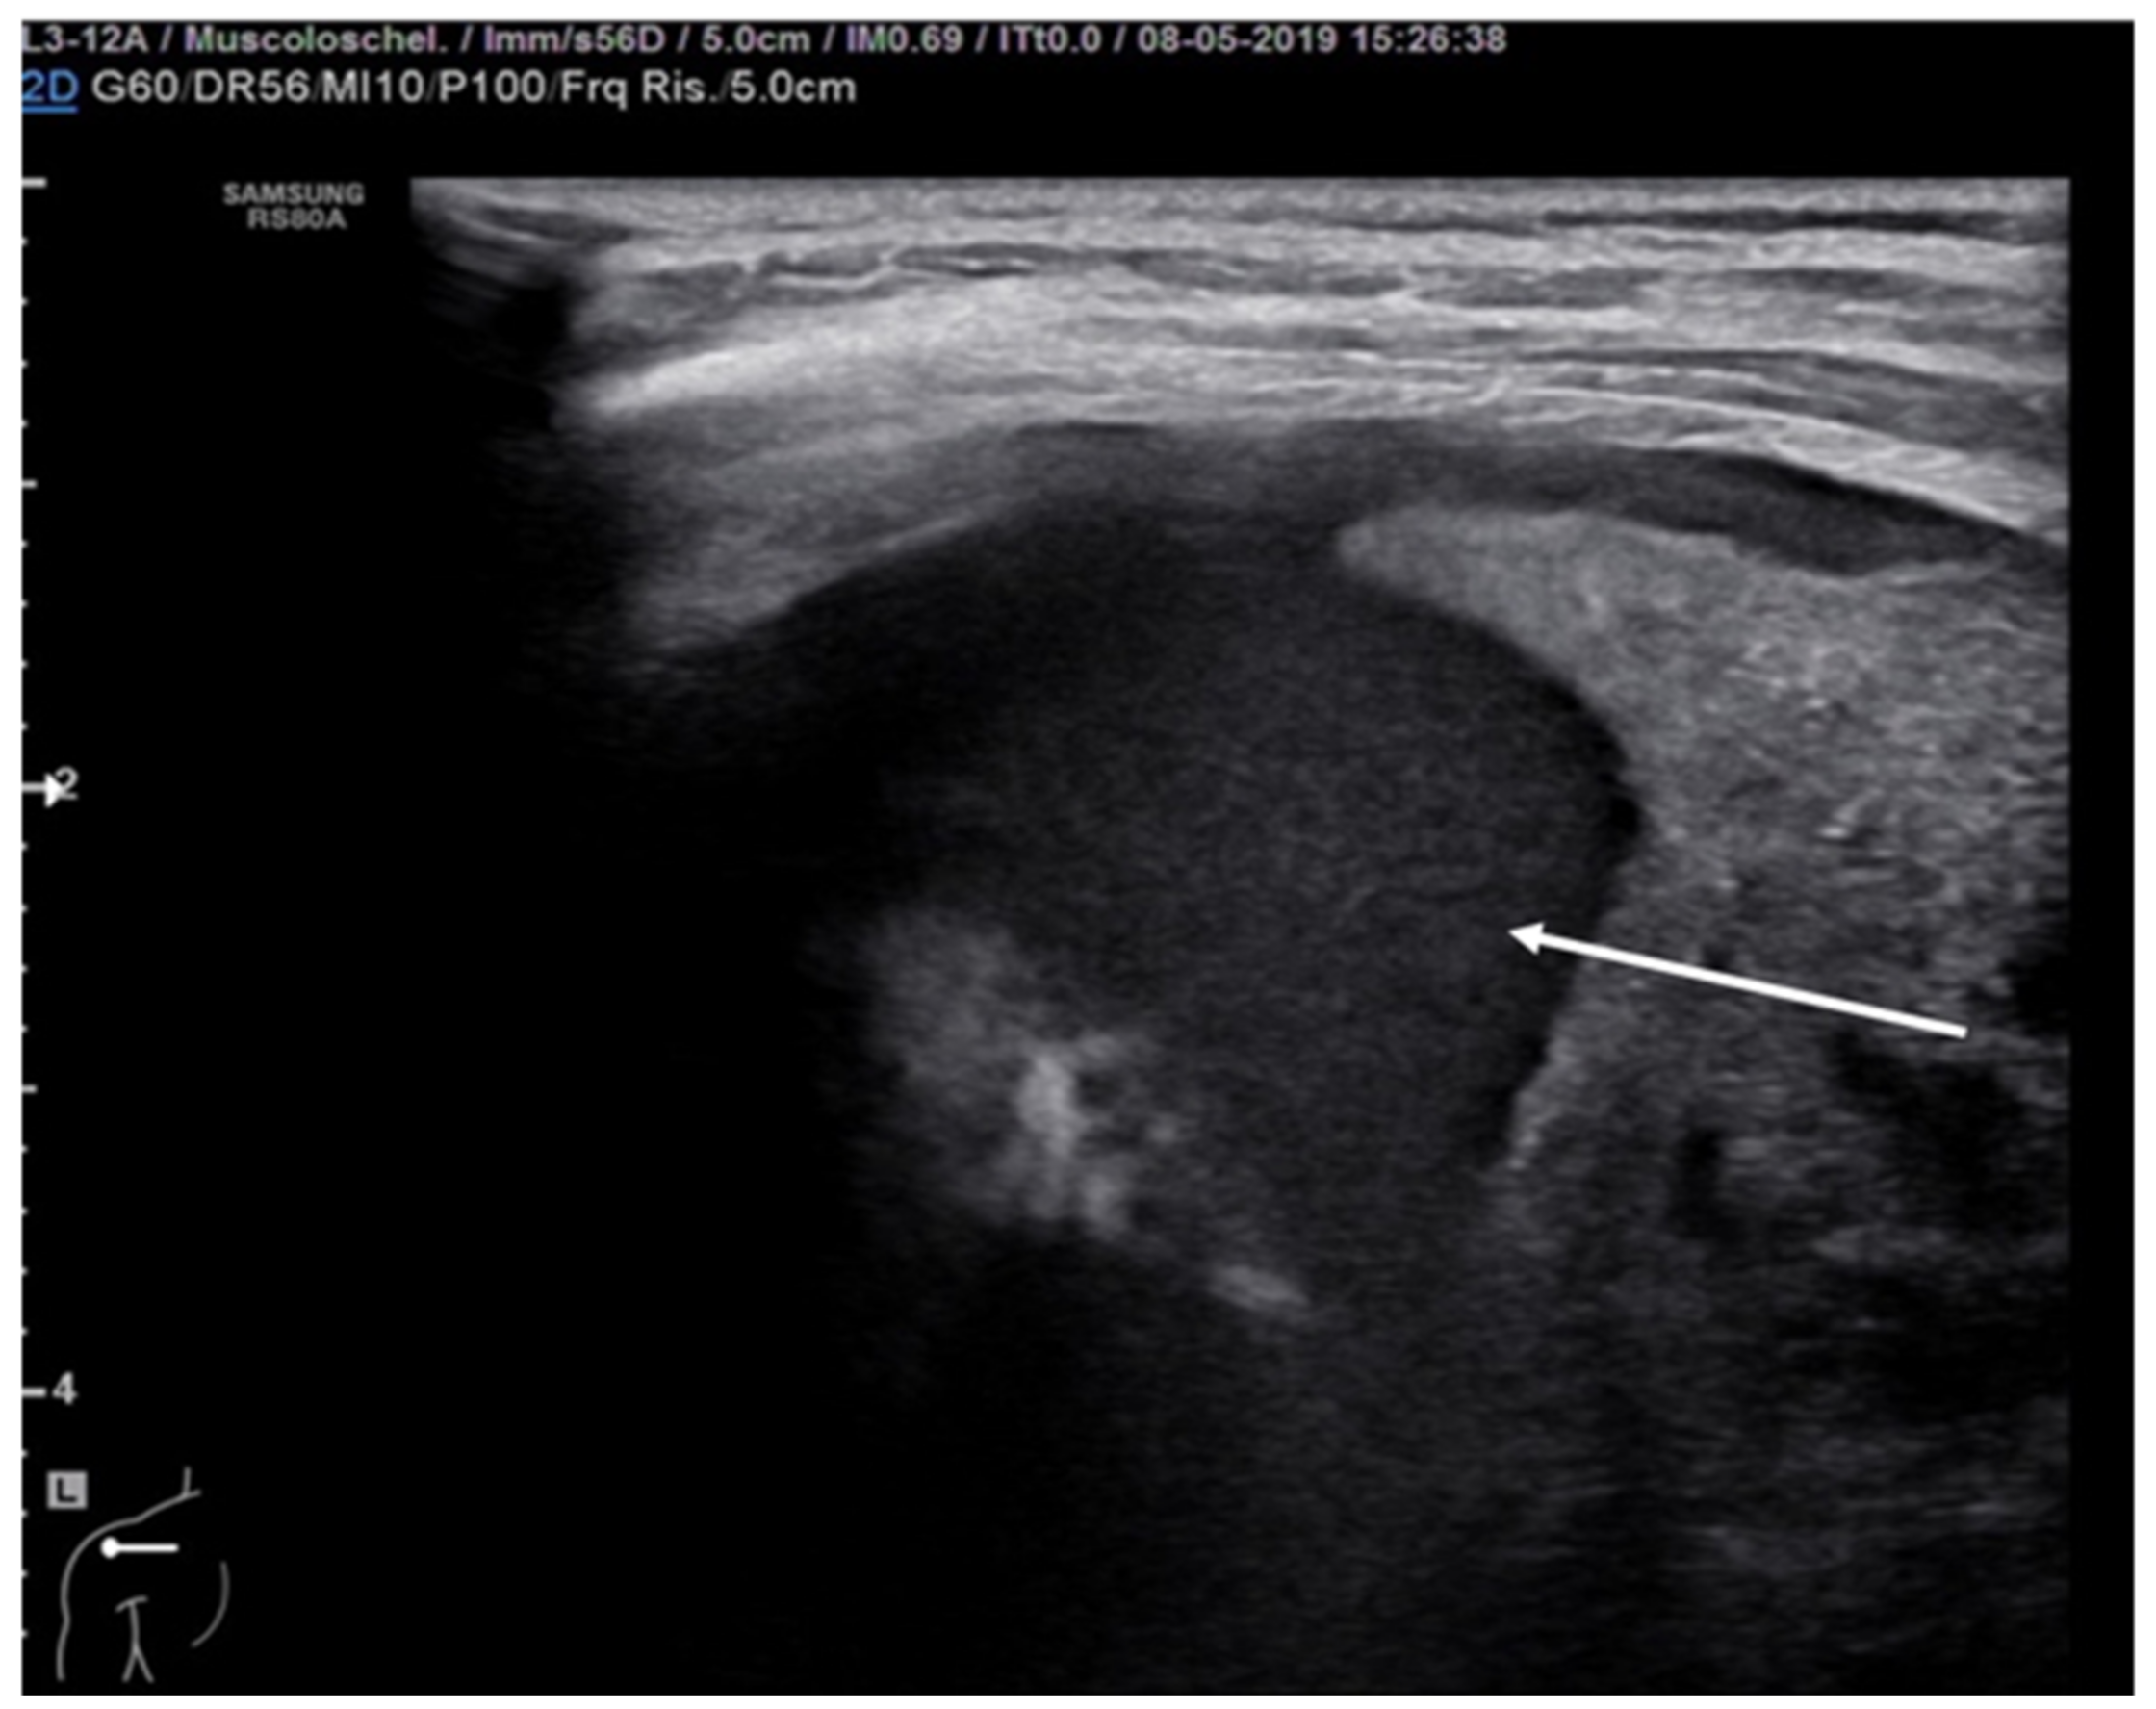

Pleural empyema refers to an infected, purulent and often loculated pleural effusion due to parenchymal infection that spreads to the pleural cavity. Ultrasound examination of the chest revealed a hypoechoic lesion with complex-septated effusions, passive atelectasis, width uniformity and smooth luminal and outer margins (Figure 12). Color Doppler can be used to differentiate the peripheral air-fluid abscess from empyema. In fact, color Doppler ultrasound vessel signals in pericavitary consolidation are a predictor of lung abscess [57,58,59,60].

Figure 12. Hypoechogenic and highly corpuscular collection suggestive of pleural empyema (white arrow).